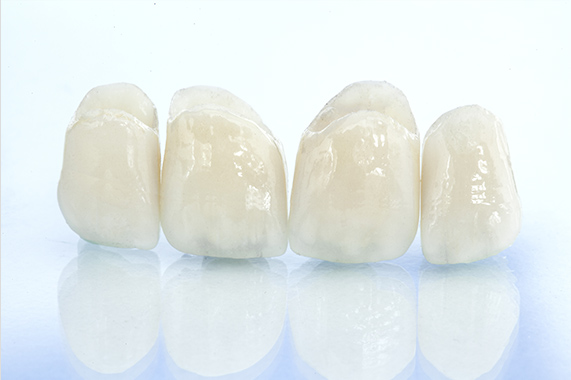

できるだけ「削らない・抜かない」を

追求した精密なアプローチ

天然の歯をできるだけ長く残すため、綿密な治療計画のもと慎重に処置を進めています。歯を削る際は、5倍速コントラを用いて振動や音を抑え、患部の場所のみを切削するだけにとどめます。また、カリエスチェックなどを使用しむし歯の範囲を精密に確認し、スプーンエキスカベーターで感染部位のみを丁寧に除去。「守る治療」で、大切な歯をできる限り残します。